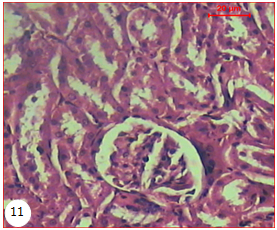

Light microscopy observations of HC-rats revealed, mild glomerular injury with mild vascular and inflammatory changes, signs of moderate vascular congestion, mesangial hyperplasia and dilatation of vascular lumen with no evidence of fat deposits (mild glomerular change), moderate tubular damage, that is, desquamated and/or vacuolated tubular epithelial cells, was noted as well (fig. 11).

Fig. 11: Micrograph of the kidney of HC rat showing hypotrophy of the glomerulus that associated with wide urinary space. Note the epithelial detachment of the renal tubules and cellular debris in the lumen of the tubules (H & E X 150) |

Treatment of HC-rats with algal extracts and fluvastatin showed, milder tubular injury, no glomerular or tubular alterations, no basement membrane thickening and fibrosis were discerned. Furthermore, normal histology of the glomerulus with well-spaced tubules, no congestion, and no inflammation was detected (fig. 12, 13 and 14 respectively).

Light microscopy observations of HC-rats also revealed mild glomerular injury with mild vascular and inflammatory changes, signs of moderate vascular congestion, mesangial hyperplasia and dilatation of vascular lumen with no evidence of fat deposits (mild glomerular change), moderate tubular damage, that is, desquamated and/or vacuolated tubular epithelial cells.

Treatment of HC-rats with algal extracts and fluvastatin showed, milder tubular injury, no glomerular or tubular alterations, no basement membrane thickening and fibrosis were discerned. Furthermore, normal histology of the glomerulus with well-spaced tubules, no congestion, and no inflammation was detected.